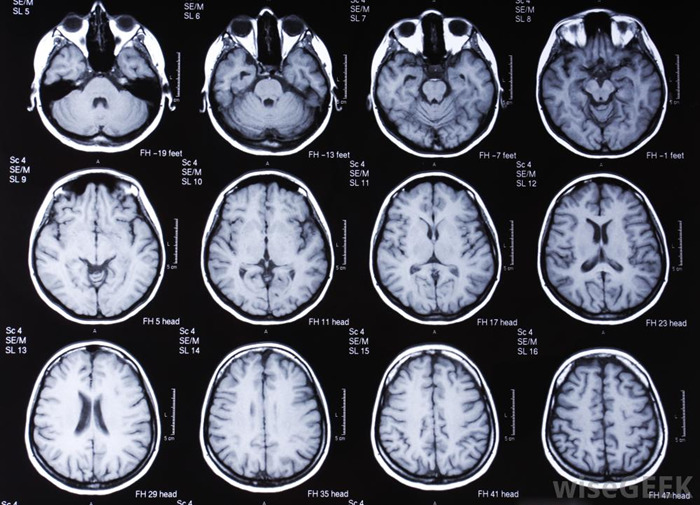

- Топография и рентгенография помогают оценить состояние головного мозга, а также костей черепа и позвоночника.

- Электроэнцефалография (ЭЭГ) позволяет выявить патологические изменения в участках мозга.